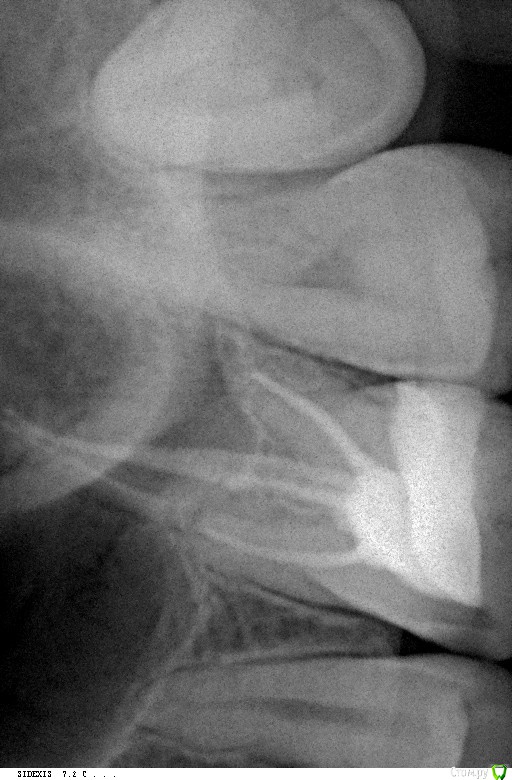

Yulia_yulia Опубликовано 1 февраля, 2017 Поделиться Опубликовано 1 февраля, 2017 Здравствуйте! Проблема: 26 зуб верхний несколько раз пломбировался (кусочек отваливался один раз). Неделю назад из-за виноградной косточки откололась снова небольшая часть и появилась дырка (видно черное пятно внутри зуба). Один день после откола было больно есть (при попадании еды внутрь дырки), сейчас норм. Не болит. На консультации сделали рентген. Врач сказал, надо чистить каналы, так как есть киста + ставить коронку и еще делать томографию этого зуба. Цена вопроса 50 тыс. руб. Для меня это сейчас очень дорого (нужно пломбы и на других зубах еще менять). Подскажите, пожалуйста, действительно в данном случае необходима коронка и чистка каналов? Или безопасно будет и пломбу поставить (или керамическую вкладку)? Если есть киста, то обязательна эта чистка? Ссылка на комментарий

St. Опубликовано 2 февраля, 2017 Поделиться Опубликовано 2 февраля, 2017 Если поставить пломбу, есть риск что снова что-то отколется, а на какую глубину и когда никто не знает. Если откалывается глубоко под десну - зуб приходится удалять. Опять же, хорошо что сейчас зуб не болит, но поскольку там есть хроническое воспаление ( то что назвали "киста") оно само по себе не пройдет и когда-то может разболеться.Т.е. все равно к лечению этого зуба придется возвращаться. 1 Ссылка на комментарий

Ирина Игоревна Опубликовано 2 февраля, 2017 Поделиться Опубликовано 2 февраля, 2017 Причиной воспаления (кисты) является инфекция в каналах, чтобы её убрать их нужно перелечить, так что без чистки каналов не обойтись. 1 Ссылка на комментарий